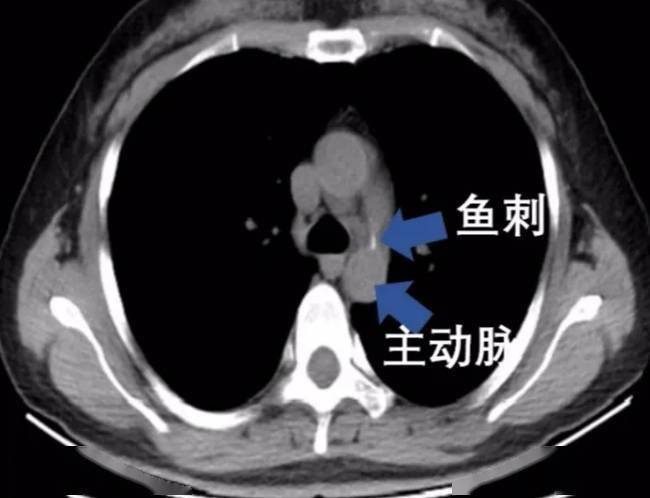

强咽鱼刺差点刺破主动脉,喝醋咽饭处理"骨鲠在喉"可能会"要命"

视而不见的鱼刺?还是我看错片子? [病例帖]